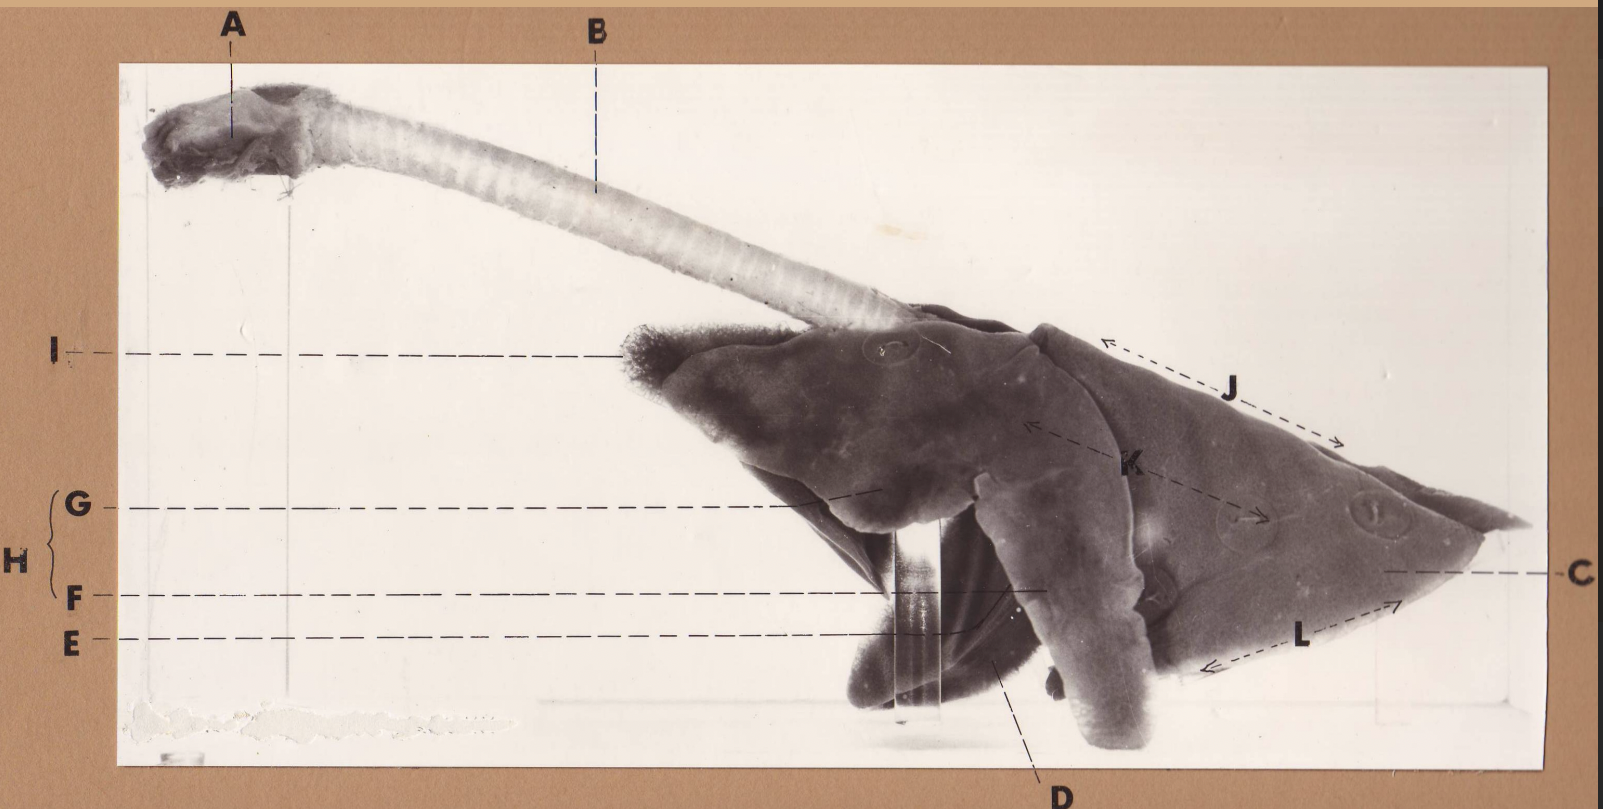

A

(cat larynx/trachea/lungs, L lateral)

larynx

B

(cat larynx/trachea/lungs, L lateral)

trachea

C

(cat larynx/trachea/lungs, L lateral)

caudal lobe

D

(cat larynx/trachea/lungs, L lateral)

middle lobe

E

(cat larynx/trachea/lungs, L lateral)

cardiac notch

F

(cat larynx/trachea/lungs, L lateral)

caudal segment, cranial lobe

G

(cat larynx/trachea/lungs, L lateral)

cranial segment, cranial lobe

H

(cat larynx/trachea/lungs, L lateral)

cranial lobe

I

(cat larynx/trachea/lungs, L lateral)

apex

J

(cat larynx/trachea/lungs, L lateral)

dorsal border

K

(cat larynx/trachea/lungs, L lateral)

costal surface

L

(cat larynx/trachea/lungs, L lateral)

basal border